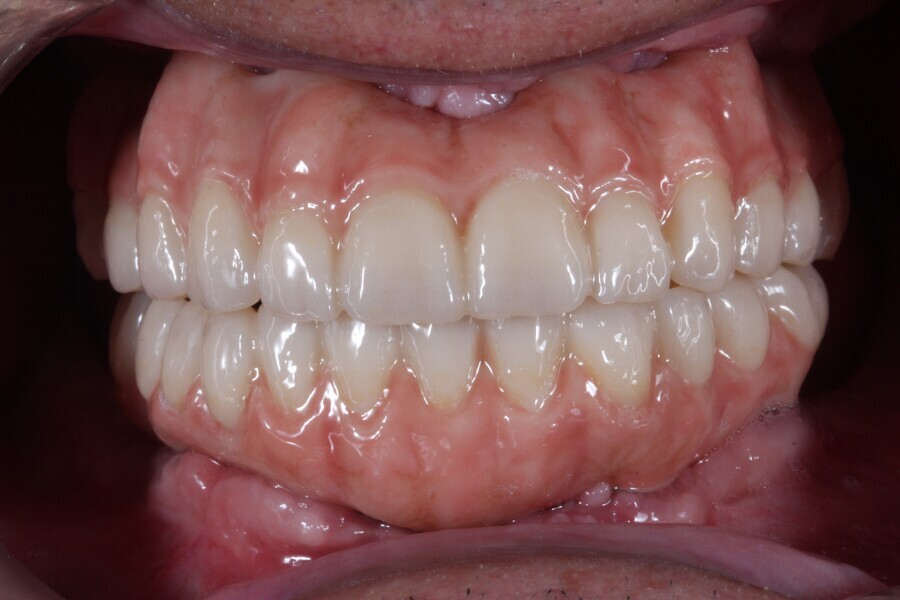

In this case, the final prostheses were fabricated using monolithic KATANA Zirconia YML (Kuraray Noritake Dental). This high-quality material offers excellent strength, durability and aesthetics for dental restorations. The staining process was performed using CERABIEN ZR FC Paste Stain (Kuraray Noritake Dental) to achieve a natural appearance and blend seamlessly with the patient’s existing dentition. PANAVIA V5 in the shade Opaque and CLEARFIL CERAMIC PRIMER PLUS (both Kuraray Noritake Dental) were used to cement the bases (Elos Accurate Hybrid Base H Non-Engaging compatible with Straumann Standard and Standard Plus 4.8 mm diameter, regular neck implants; Elos Medtech; Figs. 15–22).

Fig. 17: The nal prosthesis on the day of delivery.

Fig. 18: Final prostheses of monolithic KATANA Zirconia YML, stained using CERABIEN ZR FC Paste Stain. The dark gingiva spots were stained with the shade Red, the light pink surfaces with the shade Pink and the highlights with the shade Salmon Pink.

Fig. 19: Final prostheses, right side view. The cervical parts were stained with the shade Cervical 2, the incisal two thirds of the anterior teeth with the shade Grayish Blue and the mamelons with the shade Mamelon Orange 1.

Fig. 20: Final prostheses, left side view.

Fig. 21: Final maxillary prosthesis, occlusal view.

Fig. 22: Final mandibular prosthesis, occlusal view.